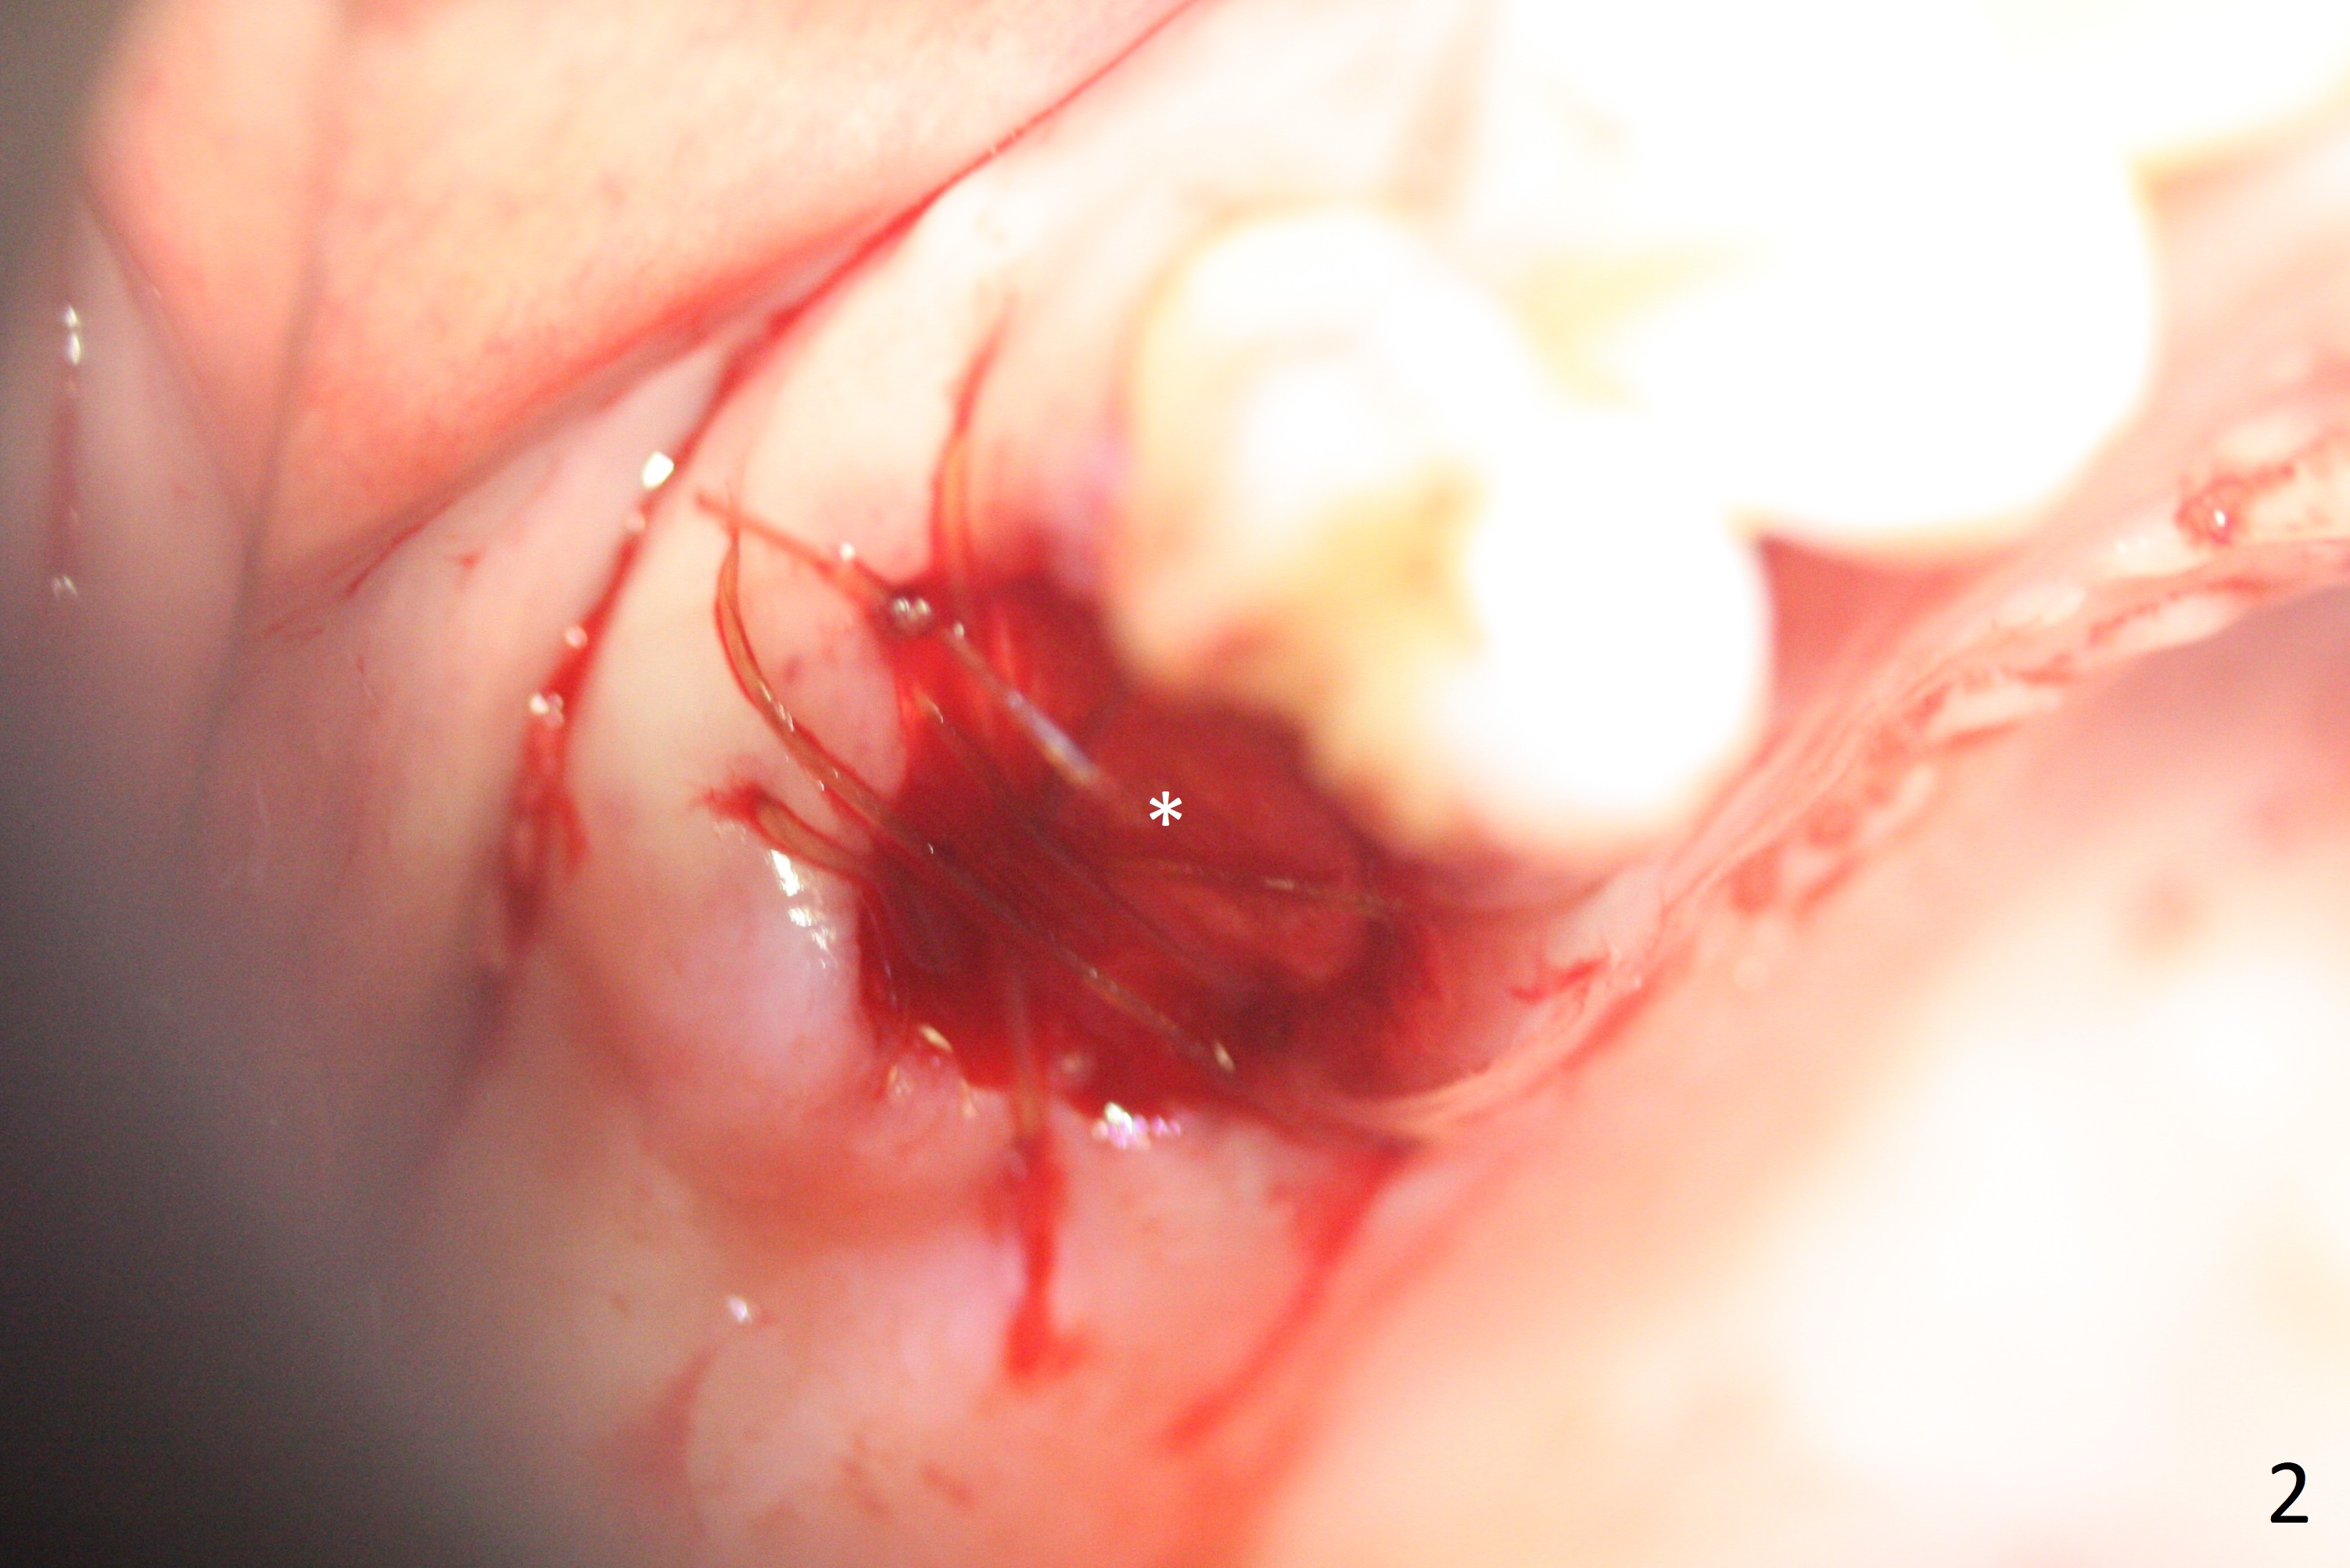

A 53-year-old woman wants to extract the tooth #3 with recurrent apical periodontitis (Fig.1). Socket preservation is conducted (Fig.2). The tooth is terminal in the arch and difficult to keep periodontal or acrylic dressing in place. To overcome the situation, a prefabricated space maintenance is placed without cementation because of its inherent fitness (Fig.3). Periodontal dressing (Fig.4 D) appears to be retained in place. The spacer is lost prematurely due to no cement, but the wound appears to be healing 13 days postop (Fig.5,6). The socket heals 3 months postop (Fig.7,8). However the ridge is narrow 19 months postop (Fig.9, as compared to that of the tooth #14 (Fig.10)).